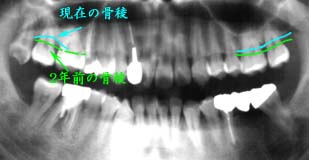

| 48歳 男性 (国籍:中国) | ||

| 全体に縁下歯石の沈着が著明で、 歯冠部全体にプラークの付着が あり清掃状態も不良 |

来院毎にスケーリングを 繰り返した |

歯冠部全体に付着していた プラークも徐々に減少し、 清掃状態も比較的良好 |

処置および処置方針:

主訴である欠損部の処置を行うかたわら、来院毎にスケーリングを繰り返した。

カリエス治療優先ではあったが、治療進行にともない歯周疾患の臨床症状も改善された。

当初、来院のたび歯冠部全体に付着していたプラークも徐々に減少し、6ヵ月後には清掃状態も

比較的良好となった。